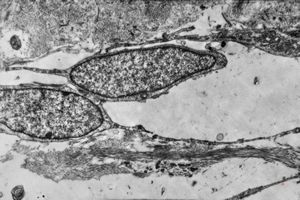

F,42y. | pseudoangiomatous hyperplasia